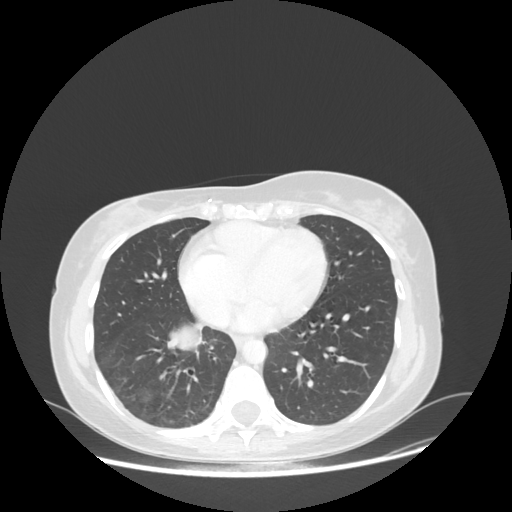

Original NATIVE CT scan (input)

Full window (WL 1023.5, WW 4095 β†’ Low βˆ’1024, High +3071)

Lung window (WL -600, WW 1500 β†’ Low βˆ’1350, High +150)